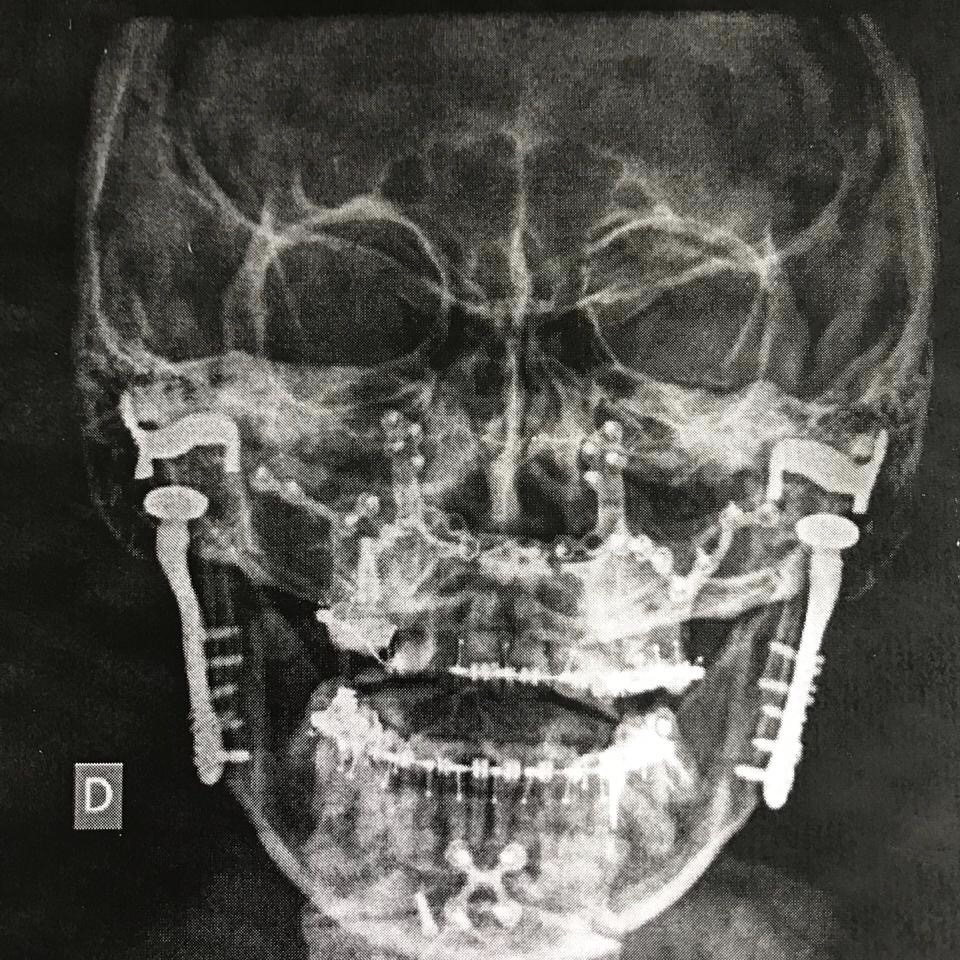

No começo durou 4 meses, já estávamos em 2017, fiz 3 infiltrações porque as 2 anteriores não fizeram o efeito necessário. Até que Deus iluminou meu caminho e a Patricia Zelante Veras compartilhou a história dela. Eu voei do MT (Mato Grosso) para São Paulo e fui consultar com o Dr Roberto Piteri, já era novembro de 2017. Esses anjos de Deus me ajudaram muito. O plano demorou a liberar e não cobria a equipe porque não eram médicos mas uma especialidade da odontologia. Diagnóstico: reabsorção dos côndilos mandibulares, uma degeneração bilateralmente.

A dor já estava absurda e eu não tinha mais vida. O que acelerou mais ainda o processo foi o queixo pequeno demais. Era operar ou operar. Eu alternava entre codeína, tramal e morfina. Meu fígado e meu estômago ficaram arrebentados e eu já estava psicótica de tanto analgésico. Finalmente, operei em 15/11/2018 depois de 2 anos de dor e lágrimas. Do momento em que acordei da anestesia até agora eu não tive mais dor na ATM. Nem acredito que hoje eu tomo umas gotinhas de dipirona apenas! Estou explodindo de felicidade.

Claro que não foi fácil porque a cirurgia foi super invasiva e eu senti as crises por ter que suspender os remédios da artrite para poder operar. Mas valeu muito à pena! Gente, muitos fazem artroplastia no quadril, ombro, joelhos, acrescentem a ATM na lista. E digo que não é plaquinha de bruxismo ou aparelho que resolvem. Precisamos de atendimento interdisciplinar e de profissionais que possam entender nossa condição.Quem precisar de ajuda pode contar comigo.